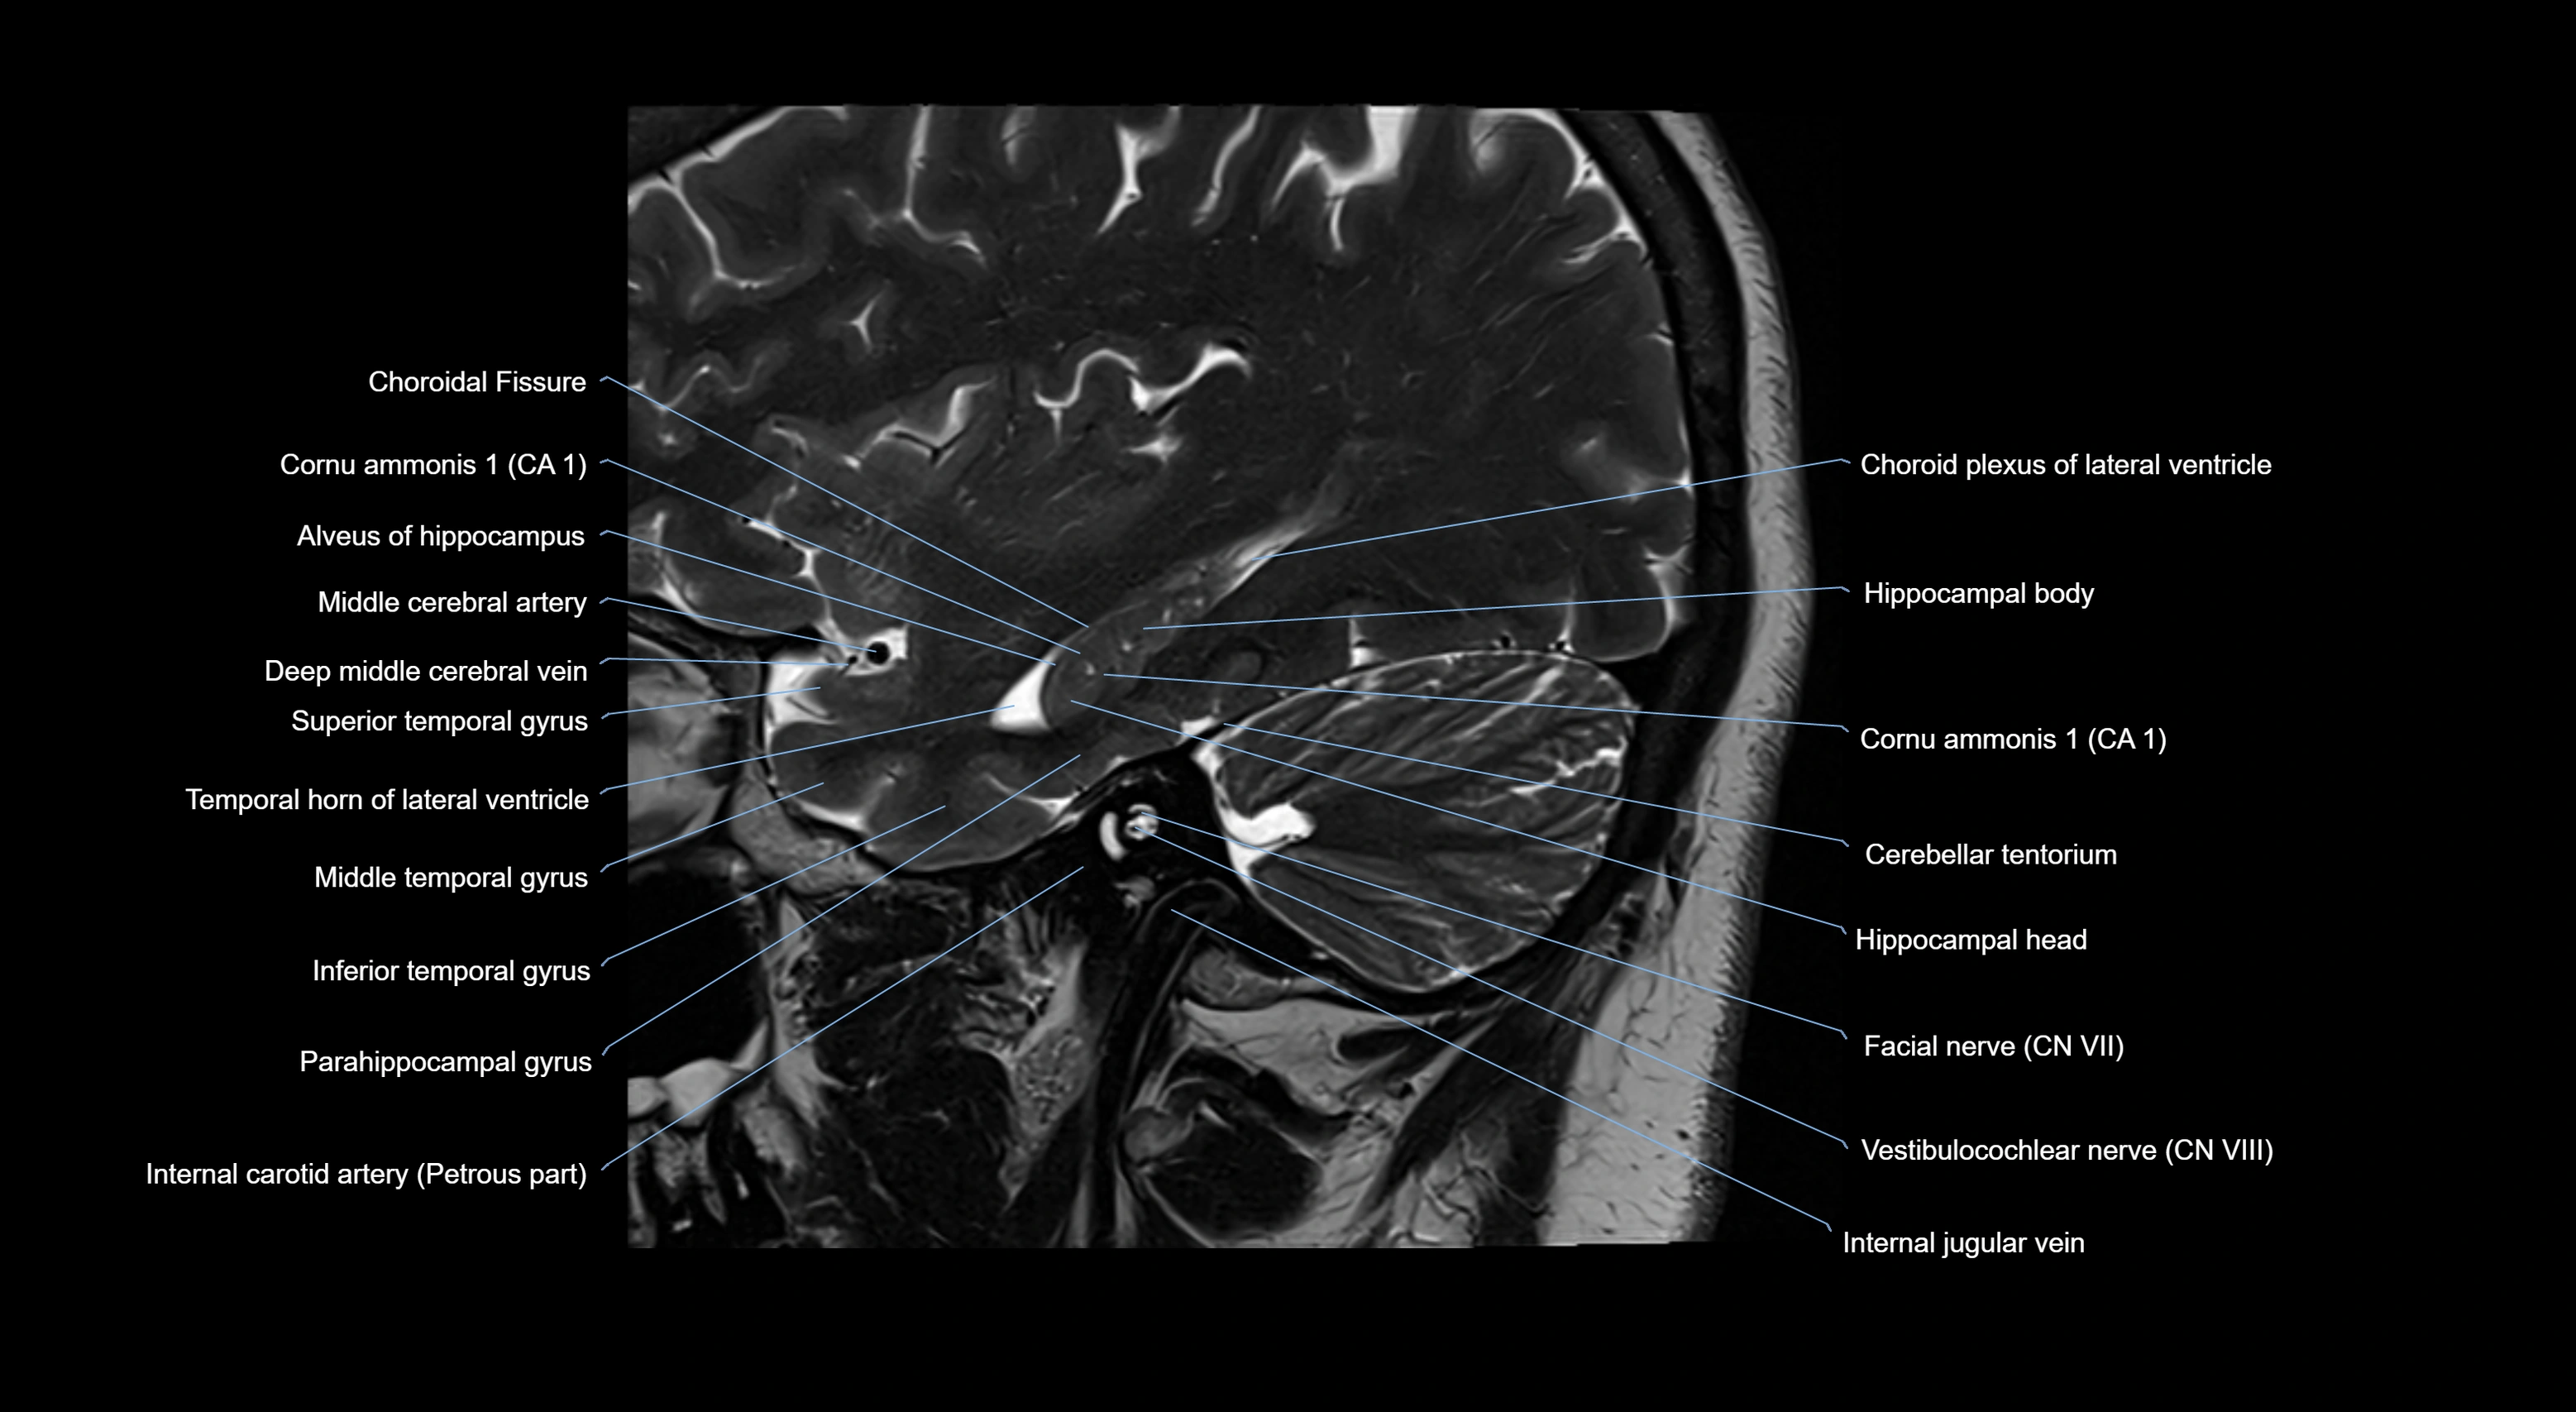

MRI images